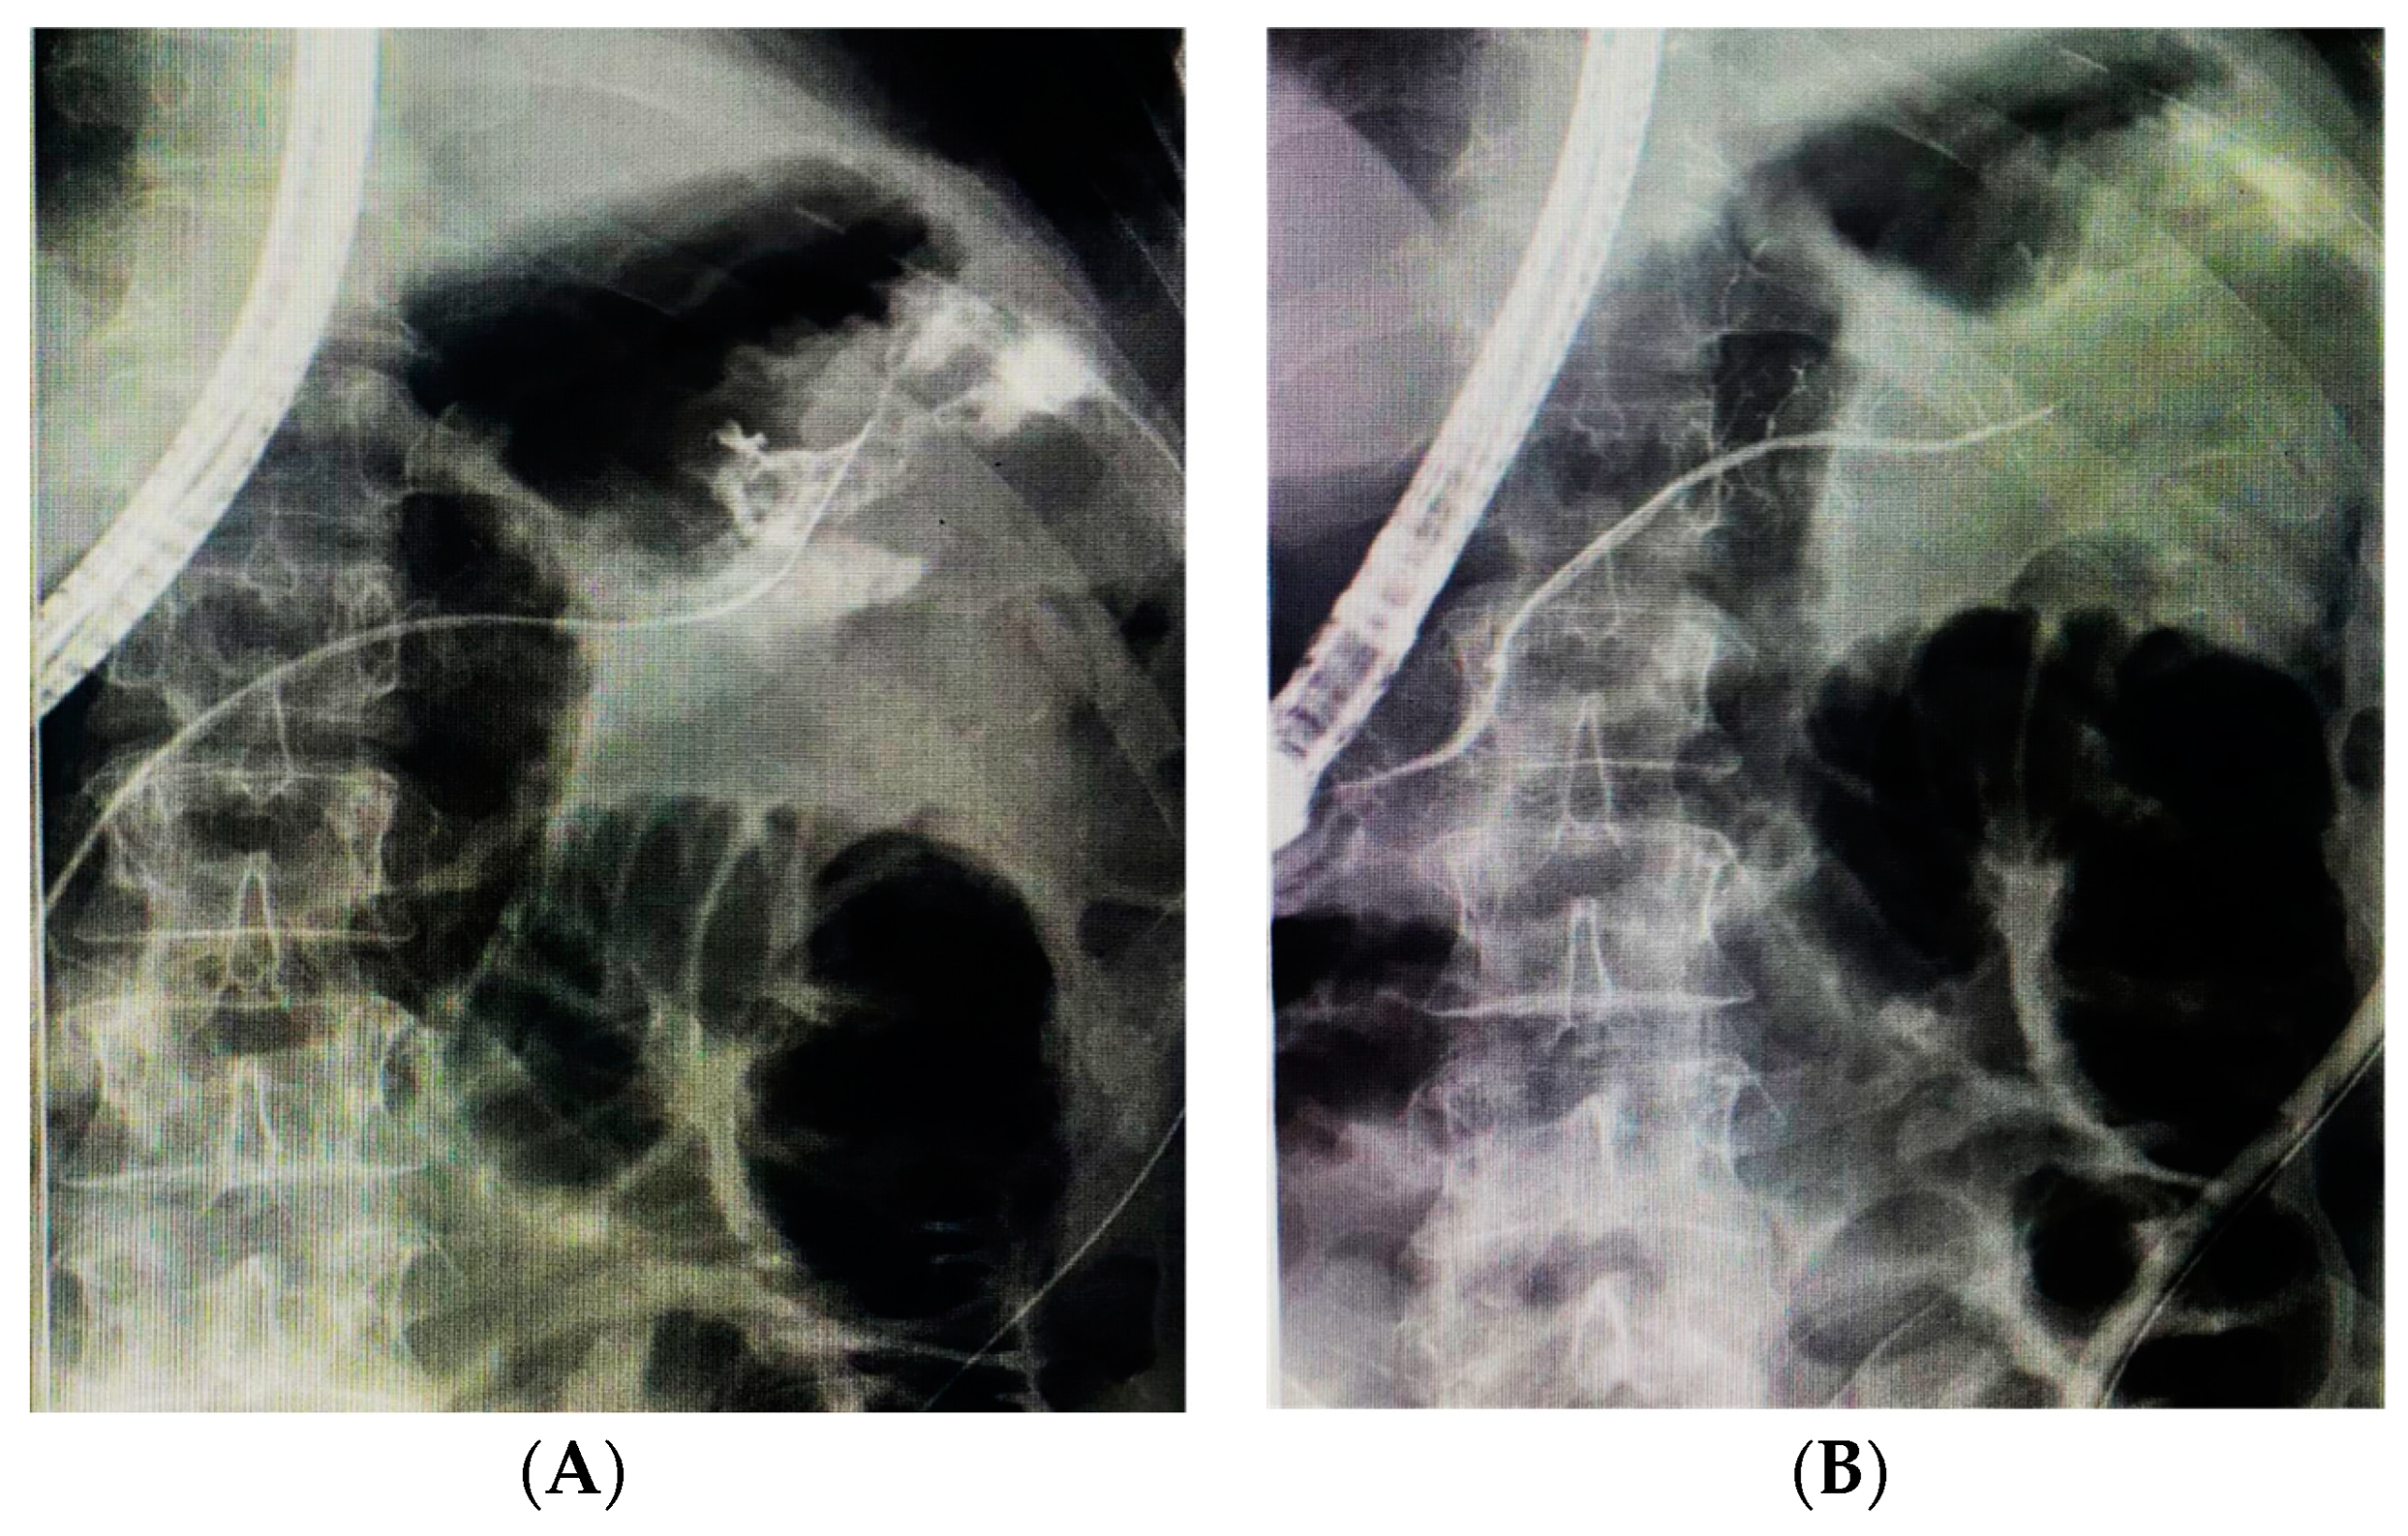

3.1. Pancreatic Duct Leak